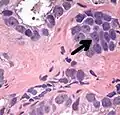

Small-cell carcinoma 0.3–2%[14][15][notes 1]

• Small blue cells with scant cytoplasm[1]

• High nucleus/cytoplasm ratio[1]

• "salt and pepper" chromatin[1]

• Nuclear molding[1]

• Necrosis of single cells, or geographic[1]

• Smearing artifacts[1]

Half of cases have usual acinar components[1]